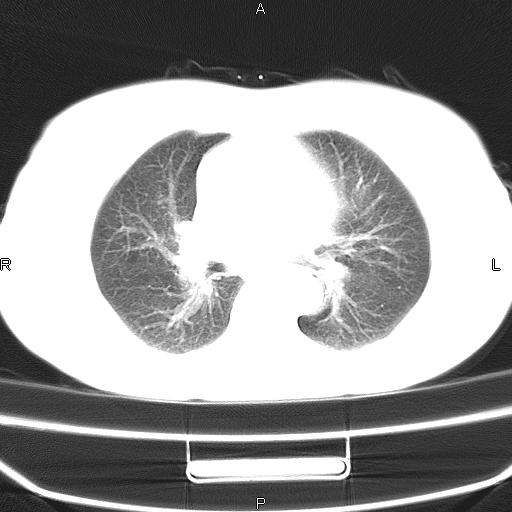

患者,女,66岁。健康体检胸部透视发现右上肺片状阴影。既往无不适,患者自诉三个月前曾有低热病史体温37.5左右一周。用药后缓解。至今无其它不适。请老师们指导指导。

考虑:右肺上叶周围型肺癌(分叶状肿块+砂粒状钙化+胸膜尾征)。

病灶见明显分叶、大小较大(大于3cm?),老年人,多考虑:肺癌,建议穿刺活检。

典型的中心型肺癌,尖段支气管阻塞。

以下是引用dyqct在2010-6-3 9:32:00的发言:[br]考虑:右肺上叶周围型肺癌(分叶状肿块+砂粒状钙化+胸膜尾征)。

不像中央型啊

结合病史不除外感染性病灶。

右肺上叶周围型肺癌可能性大。

考虑:右肺上叶周围型肺癌